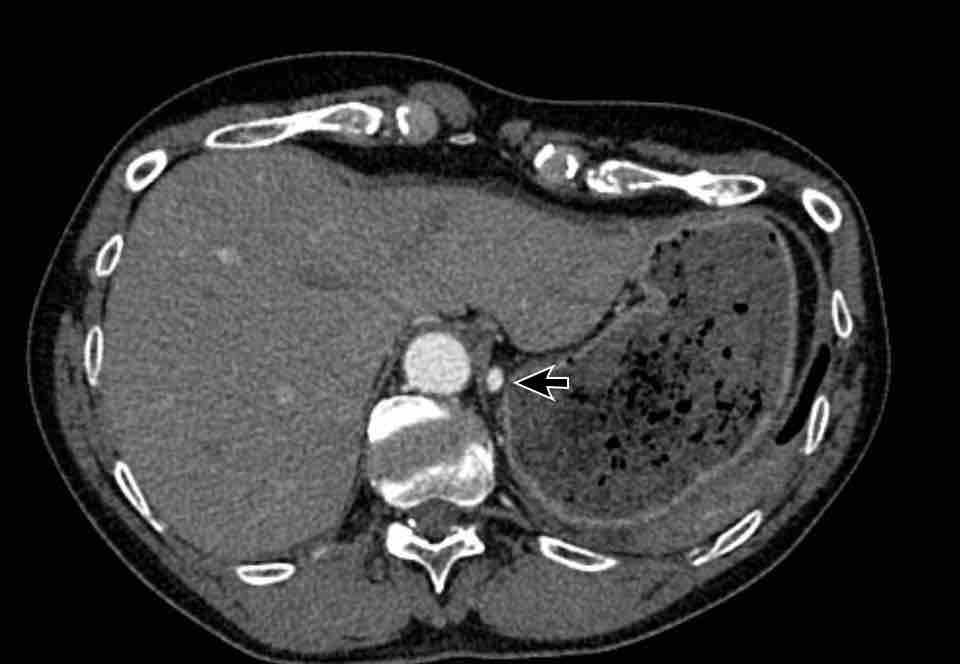

Hình ảnh

Bệnh nhân này được lên kế hoạch cắt thùy trên phải do ung thư phổi và bất thường mạch máu này ban đầu đã bị bỏ sót trên hình ảnh CT.

Những hệ quả trong phẫu thuật của bất thường như vậy nhấn mạnh tầm quan trọng của việc không bỏ sót các biến thể này.

PAPVR bên trái phát hiện tình cờ với dẫn lưu trên tim của máu từ thùy trên trái vào tĩnh mạch tay đầu trái (các mũi tên).